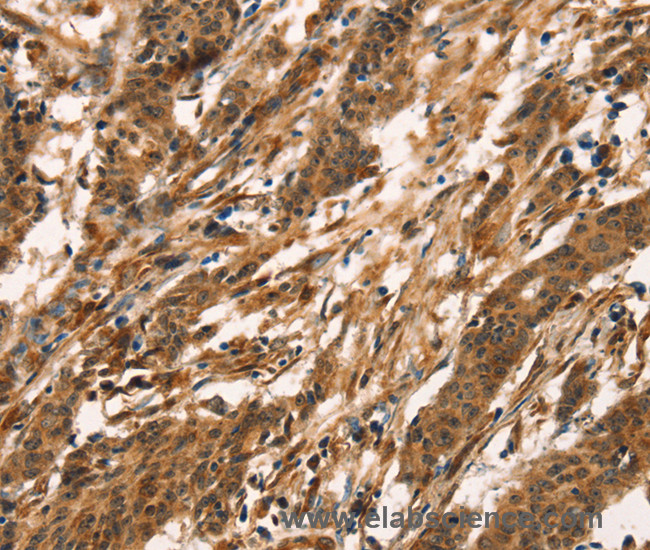

Conversion and usertracking via Google Tag Manager

Natural killer (NK) cells are lymphocytes that can mediate lysis of certain tumor cells and virus-infected cells without previous activation. They can also regulate specific humoral and cell-mediated immunity. The protein encoded by this gene belongs to the killer cell lectin-like receptor family, also called NKG2 family, which is a group of transmembrane proteins preferentially expressed in NK cells. This family of proteins is characterized by the type II membrane orientation and the presence of a C-type lectin domain. This protein forms a complex with another family member, KLRD1/CD94, and has been implicated in the recognition of the MHC class I HLA-E molecules in NK cells. Protein function: Plays a role as a receptor for the recognition of MHC class I HLA-E molecules by NK cells and some cytotoxic T-cells. [The UniProt Consortium]

Anti-KLRC1, Anti-NKG2A, Anti-CD159a, Anti-NK cell receptor A, Anti-NKG2-A/B-activating NK receptor, Anti-CD159 antigen-like family member A, Anti-NKG2-A/NKG2-B type II integral membrane protein, KLRC1 Polyclonal Antibody